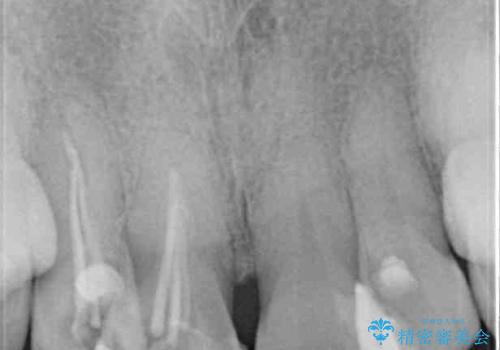

お粗末な根管治療、根管充填がされていたため、補綴治療を行うにあたり根管治療を行いました。